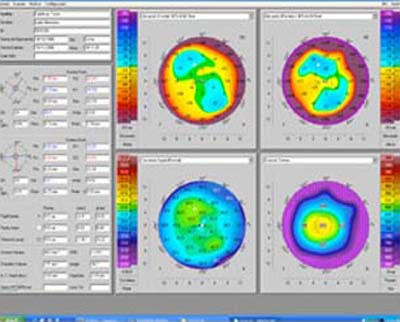

Esta tecnología ha continuado evolucionando acorde a las necesidades de la practica médica y se diseñaron otro tipo de topógrafos que realizan un barrido con hendidura de luz sobre la córnea con movimiento horizontal o rotatorio y reconstruyen luego digitalmente las imágenes captadas pudiendo de esta manera hacer reconstrucciones tridimensionales que analizan las superficies por Elevación; se conocen como Topógrafos de Elevación. Esta nueva aproximación permite también hacer el análisis de las aberraciones corneales (Foto 7) per se desarrollando las ecuaciones de Zernicke con base a las irregularidades reveladas en los mapas de elevación.

6 - Topografía

7 - Aberraciones Corneales de Foto 6

8 - Hendidura de Rotación

9 - Aberraciones Corneales de Foto 8